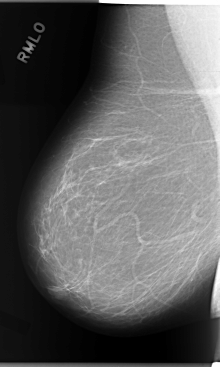

C_0114_1.RIGHT_MLO

RIGHT_CC LINES 5952 PIXELS_PER_LINE 3232 BITS_PER_PIXEL 12 RESOLUTION 50 NON_OVERLAY

RIGHT_MLO LINES 5864 PIXELS_PER_LINE 3512 BITS_PER_PIXEL 12 RESOLUTION 50 NON_OVERLAY